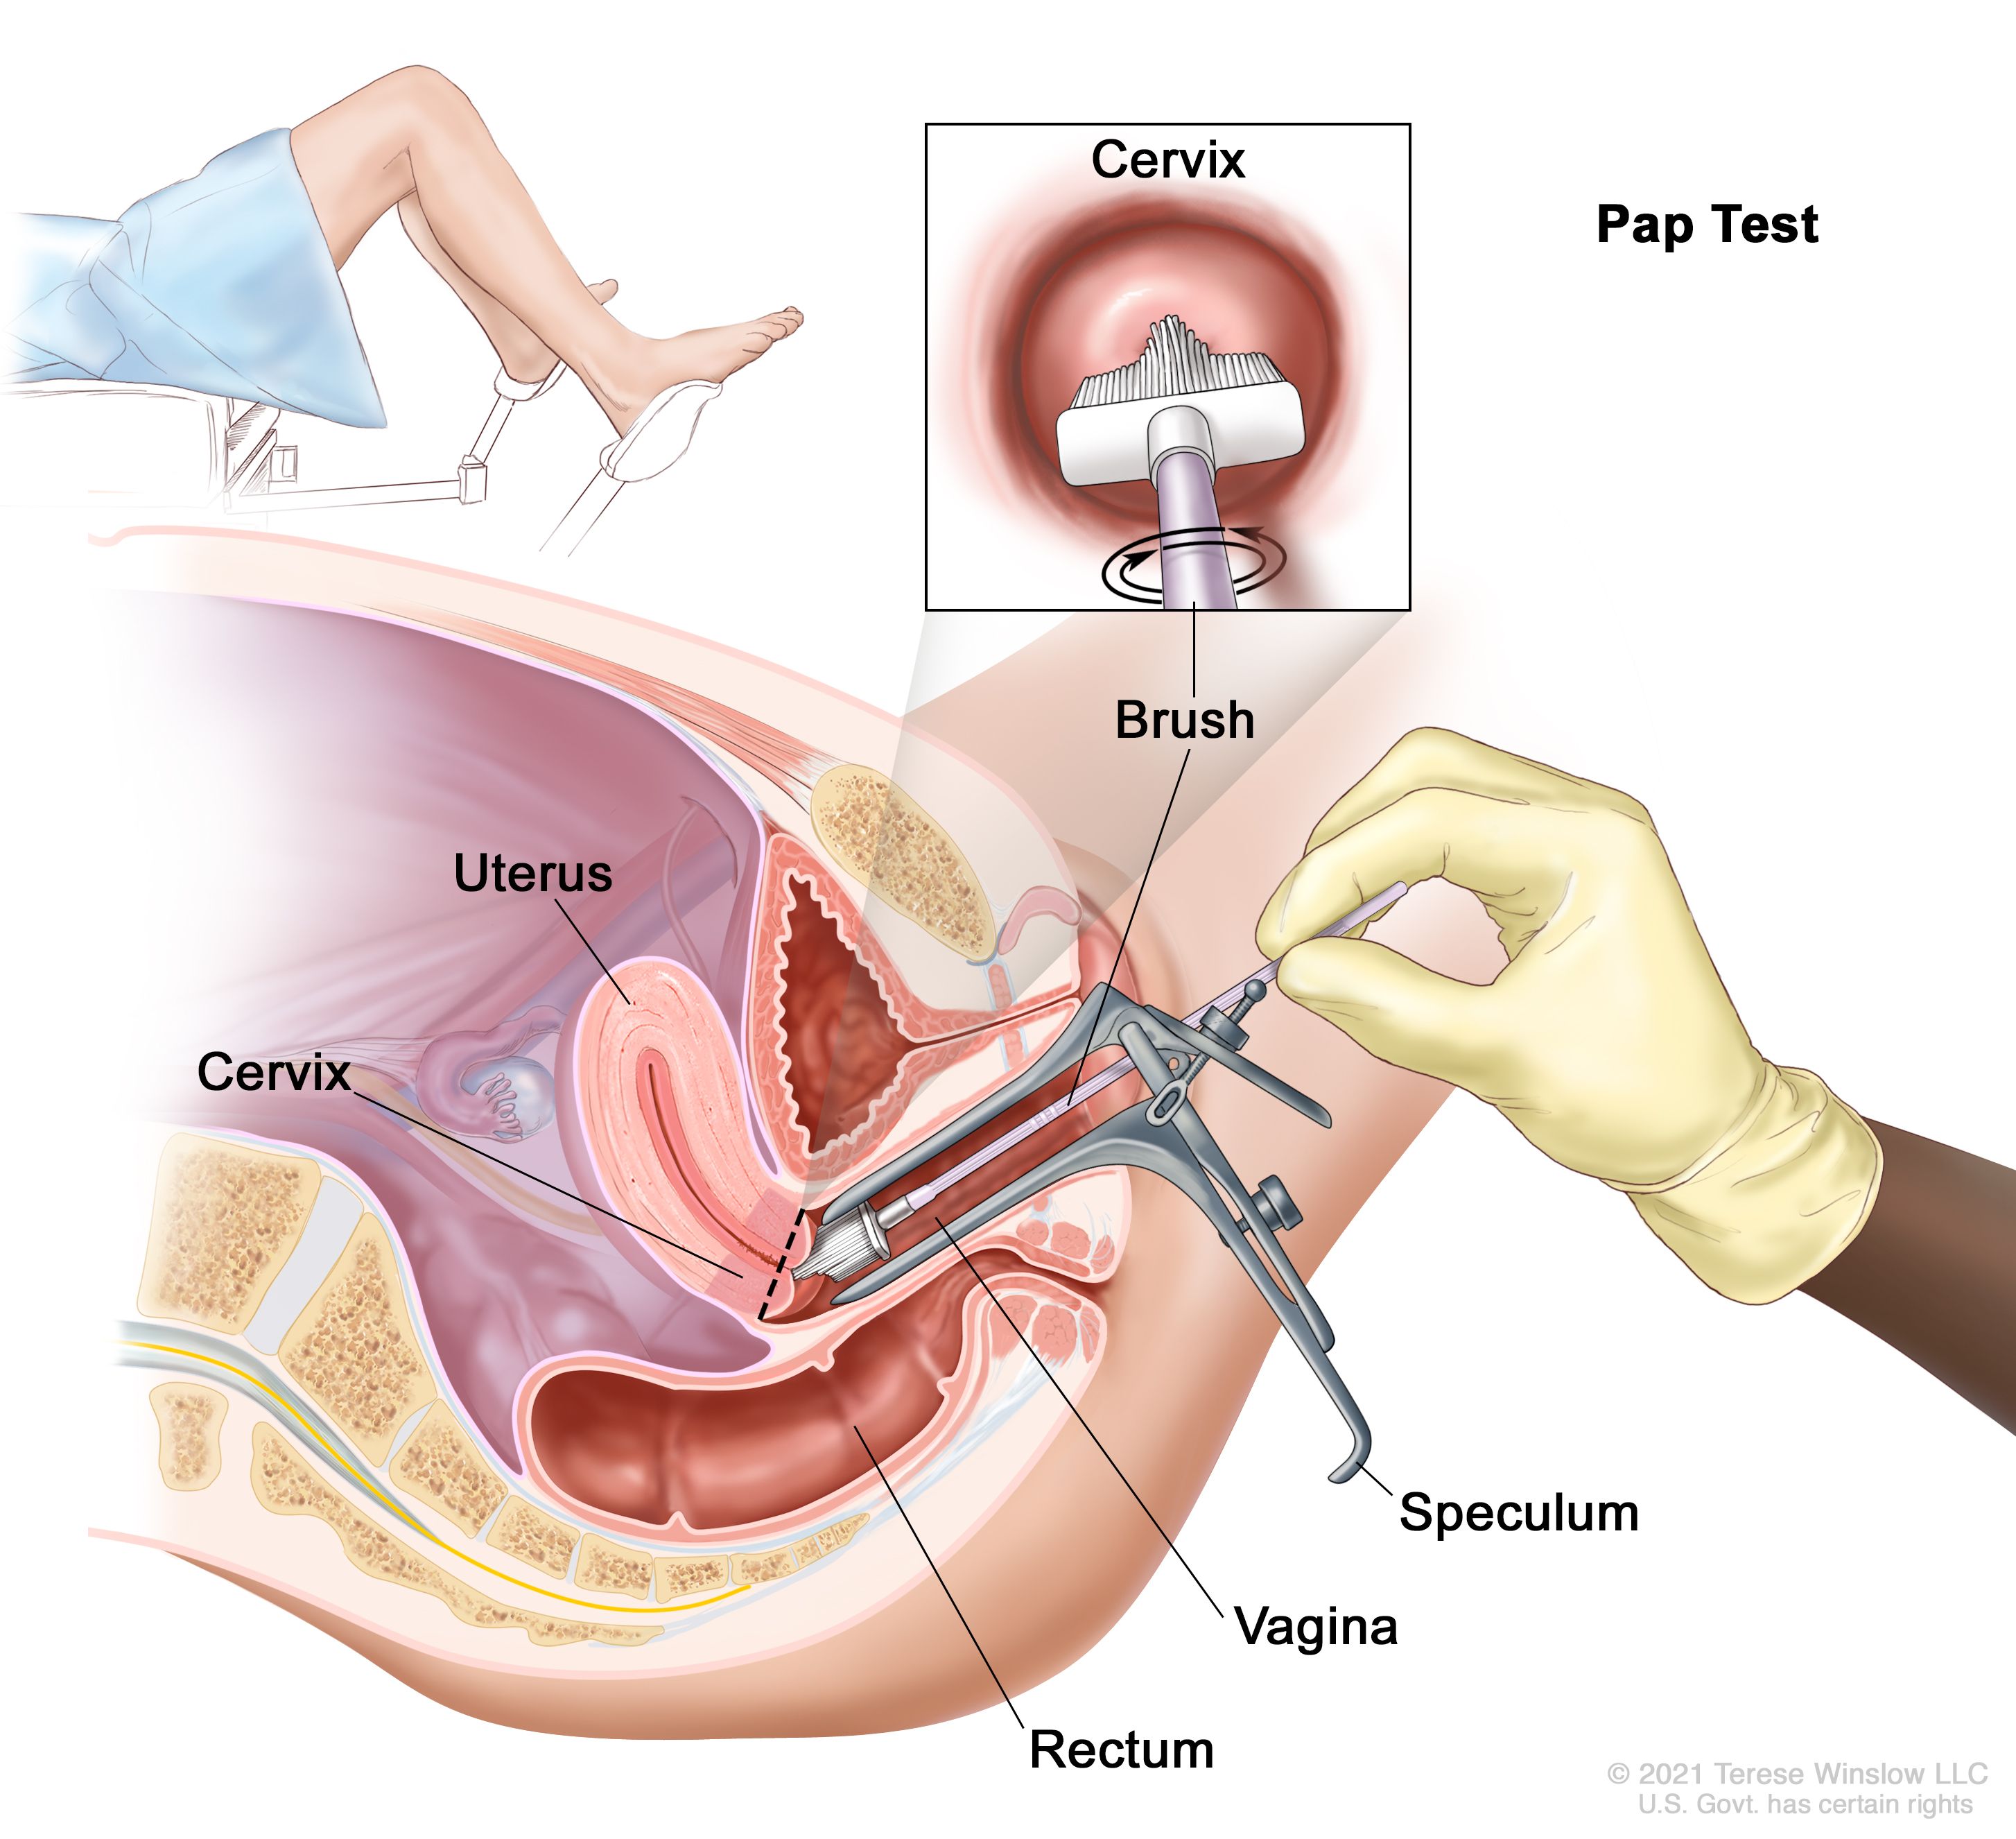

In a recent study in the journal cancer epidemiology, biomarkers and prevention had found that women who. Cryosurgery this treatment kills the cancer cells by freezing them. Ad learn more about a treatment option for advanced cervical cancer.